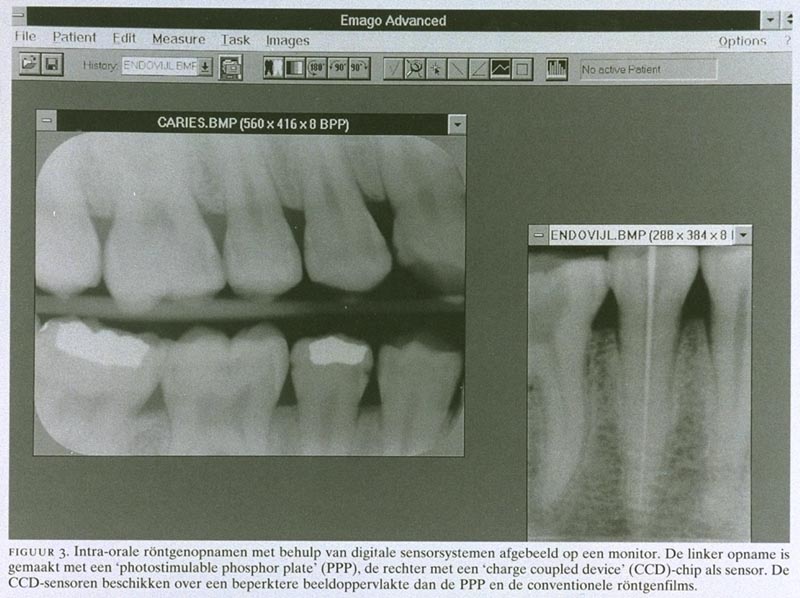

Met de introductie van de digitale radiologie in de tandheelkunde kan de blootstelling aan röntgenstraling bij intra-orale opnamen verder worden gereduceerd.5 Voor tandheelkundige toepassingen wordt het beeld bij de meeste digitale systemen vastgelegd met een ‘charge coupled device’ (CCD)-chip als sensor voor de röntgenstraling. Hiermee wordt het verkregen beeld direct op een monitor zichtbaar (figuur 3). Een andere mogelijkheid is de ‘photostimulable phosphor plate’ als detector. In vergelijking met intra-orale röntgenfilms hebben de meeste digitale systemen als groot nadeel dat de beeldoppervlakte nog zeer beperkt is. Hierdoor moeten meer opnamen gemaakt worden om dezelfde informatie te verkrijgen en wordt het voordeel van de digitale sensorsystemen, de geringere blootstelling aan straling, tenietgedaan. Een voordeel van de digitale systemen met CCD-sensoren daarentegen is de directe beschikbaarheid van het beeld. Vergeleken met de beeldkwaliteit van conventionele röntgenfilms is die van de intra-orale sensorsystemen geringer. Dit is alleen het geval bij zeer kleine afwijkingen en het is daarom de vraag of deze verschillen klinisch relevant zijn. In de toekomst zal de beeldkwaliteit van de sensorsystemen naar alle waarschijnlijkheid toenemen, door de beschikbaarheid van betere sensoren en computers. Wanneer deze systemen minder kostbaar zijn, zal de balans mogelijk in het voordeel van de digitale sensorsystemen uitvallen, vooral door de verminderde blootstelling aan röntgenstraling.